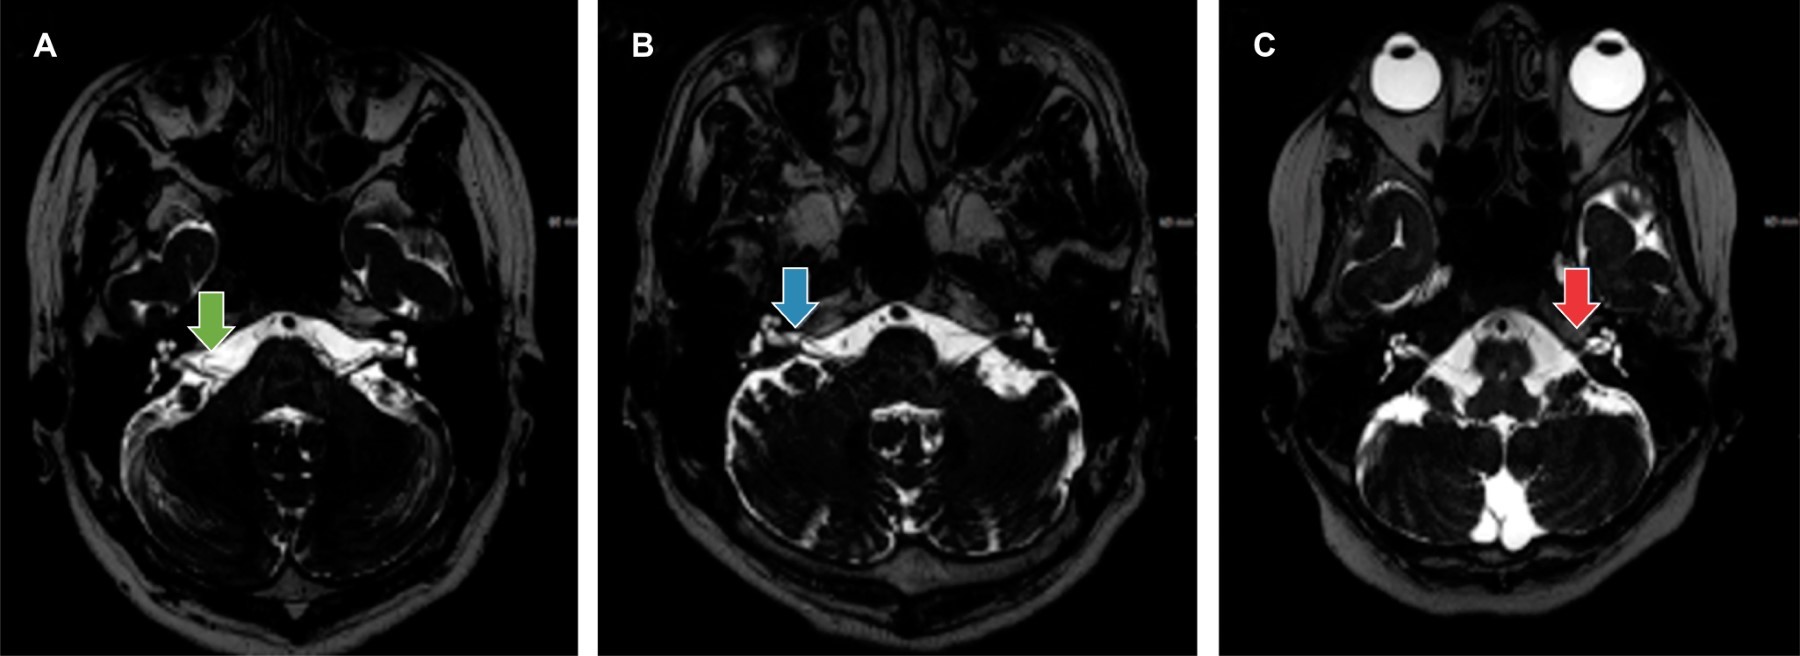

Prevalence of vascular loops of the anteroinferior cerebellar artery, in the internal auditory canal, identified by magnetic resonance imaging, at Hospital Angeles Pedregal

anteroinferior cerebellar artery, vascular loops, cerebellar pontine angle, magnetic resonance, vestibulocochlear nerve.

Introduction: neurovascular compression of the vestibulocochlear nerve by vascular loops of the anteroinferior cerebellar artery is considered a cause of neuroacoustic symptoms. Magnetic resonance imaging has contributed to assessing the vestibulocochlear nerve and the vasculature around it, with multiple advantages as it is non-invasive and provides more detailed anatomical visualization of the internal auditory canal and the cerebellopontine angle. Objective: to know the prevalence of vascular loops of the anteroinferior cerebellar artery in the internal auditory canal in the magnetic resonance studies carried out in the Magnetic Resonance Service of Hospital Angeles Pedregal. Results: 150 patients (75 women, 75 men) between 16 and 85 years old were included. 300 ears were analyzed. The most frequent loop type was grade I of the Chavda classification (right: 22.7%, left: 14%). Detection, according to the objective of the study, was focused on the brain (grade I: 24.7%, grade II: 11.3%, grade III: 5%), focused on the ear (grade I: 12%, grade II: 7.3%, grade III: 2.7%). 37% of the ears evaluated were standard. Conclusions: the vascular loops of the anteroinferior cerebellar artery are a frequent condition, demonstrating its detection in studies not only focused on the ears.

Figure 1